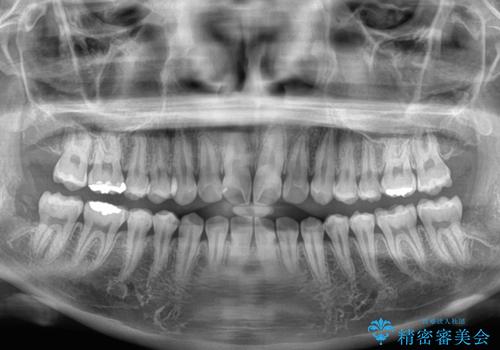

- 上下前歯部のデコボコを気にして来院された患者様です。

叢生は軽度であったため、マウスピースでもワイヤー装置でも対応可能でしたが、マウスピースを長時間使用する自信がないとのことでワイヤー装置にて矯正治療を行うこととしました。

叢生が軽度であったため、僅か半年で装置を除去することができました。